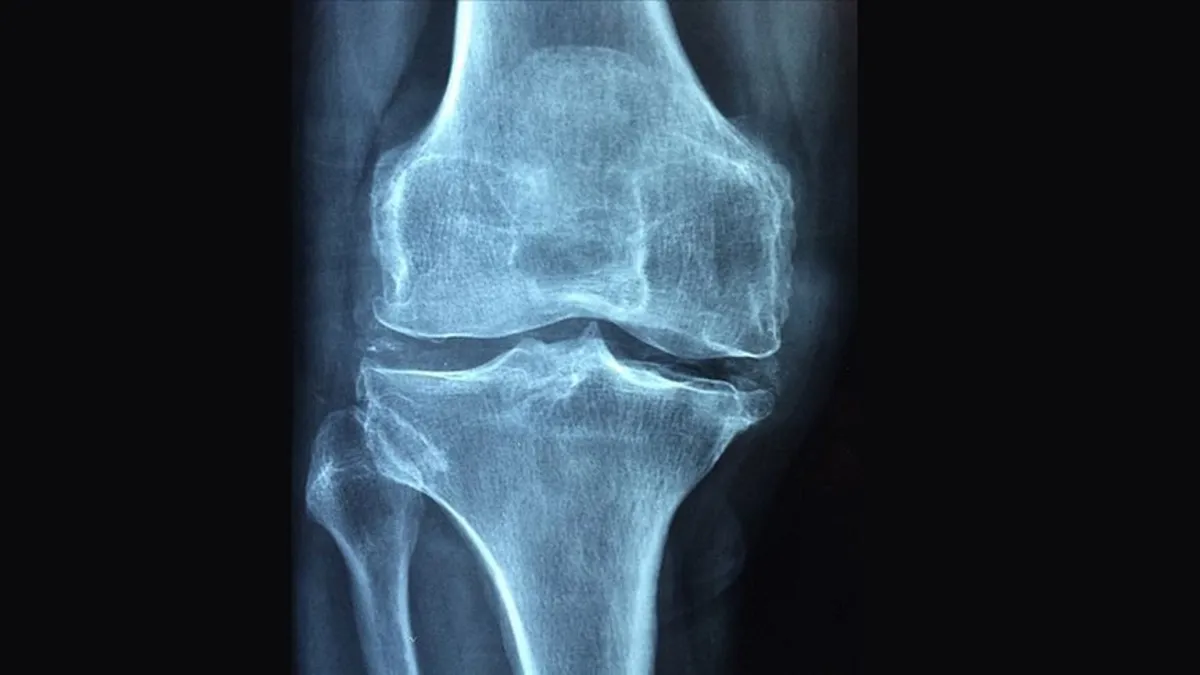

Akış Sırt bölgesinde kemik ağrısına dikkat! Kemik erimesinin 3 ay önce Sırt bölgesindeki kemik ağrısına dikkat: Erimeye işaret 3 ay önce Bilek kırıklarını göz ardı etmeyin! Bu hastalık tedavi 3 ay önce 20 Ekim Dünya Osteoporoz Günü’nde kemik sağlığına dikka 3 ay önce Kemik erimesi yatağa mahkum edebilir 3 ay önce Her 3 kadından 1’i, her 5 erkekten 1’i osteoporoz riski 3 ay önce Menopozda hormonlar yeniden düzenlenirken sistem geçici 3 ay önce Akdeniz beslenme tarzında kronik ağrıları silen, kemikl 3 ay önce Gizemli karışım ortaya çıktı! İşte kemik yapısını güçle 4 ay önce Mikroplastikler kemik sağlığını tehdit ediyor: Osteopor 4 ay önce

Sağlık takvim.com.tr Kemik erimesi belirti vermeden ilerliyor: 50 yaş üzeri mutlaka kontrol yaptırmalı 5 ay önce